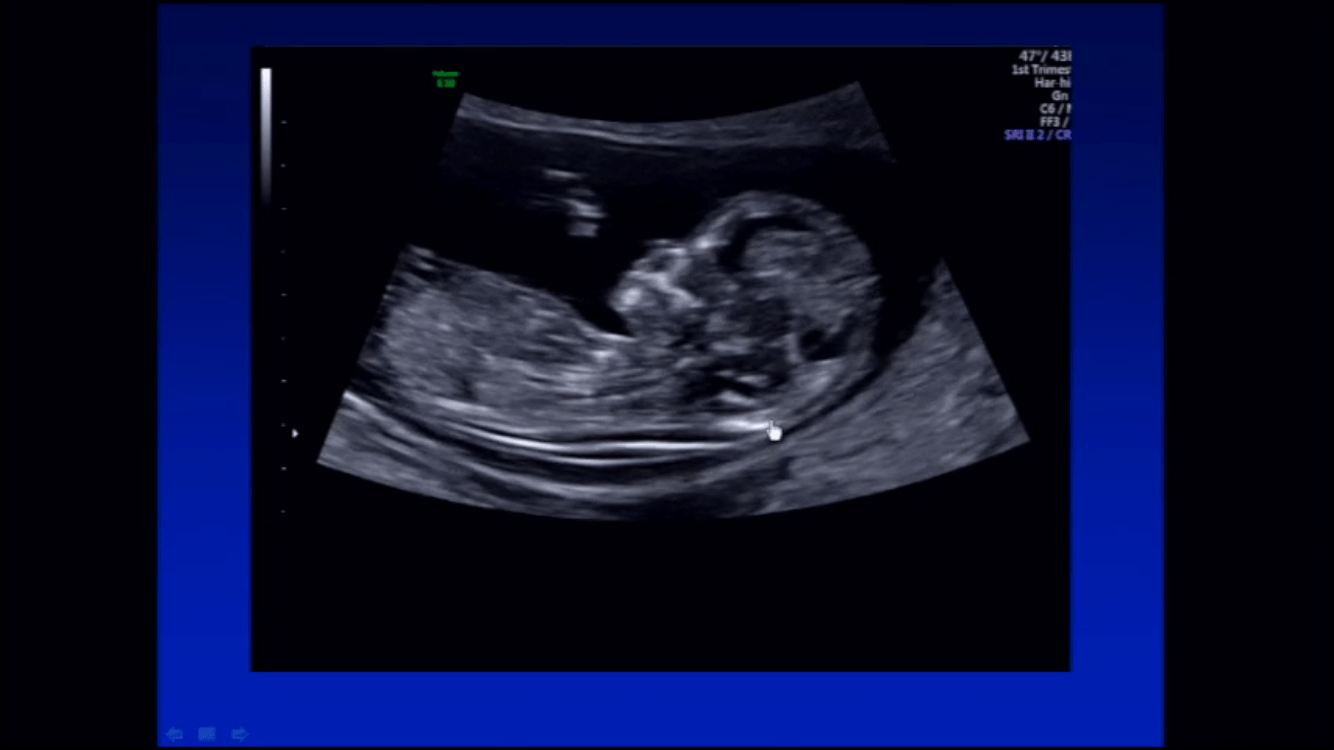

El estándar de manejo actual, establece que se ha de hacer una ecografía hacia las 12 semanas de embarazo, complementada con un análisis de sangre que es capaz de establecer el riesgo de que exista una anomalía en los cromosomas del bebé, si ésta prueba establece un riesgo aumentado, se debe hacer una prueba de estudio genético confirmatoria.

Sin embargo la capacidad diagnóstica de la ecografía, se ha ampliado y se pueden diagnosticar alteraciones anatómicas fetales mayores, ya en esta ecografía del primer trimestre, algunas de las cuales no tendrían expresión en la prueba genética.

La ecografía del primer trimestre aporta beneficios indiscutibles en el cuidado obstétrico, establece la vitalidad fetal, así como fija de manera precisa la edad gestacional, diagnostica las gestaciones múltiples, así como la anatomía de los órganos genitales e inclusive se esta estudiando el uso del doppler de uterinas en primer trimestre como marcador de riesgo de desarrollo de hipertensión en el embarazo.